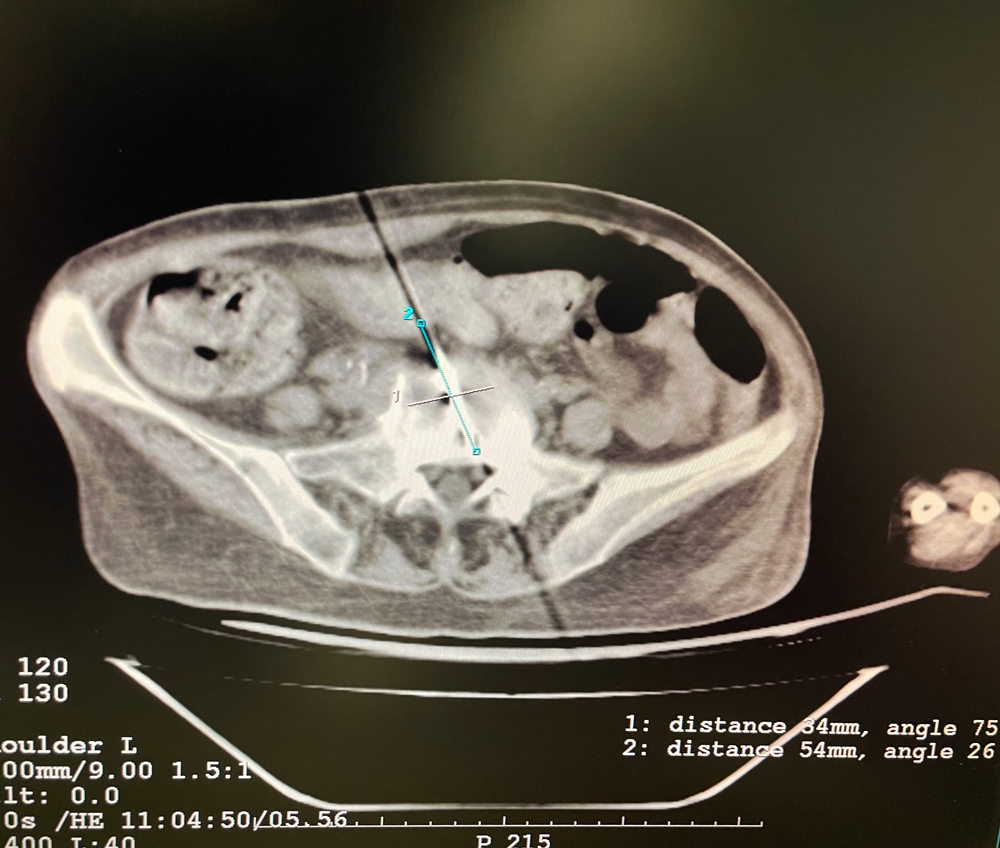

女,56歲,肺轉移瘤,骶骨、左側肋骨各一轉移灶,病灶大小均為5cm。骶骨轉移灶、肋骨轉移灶各進行2個凍融循環。患者術后狀況良好。